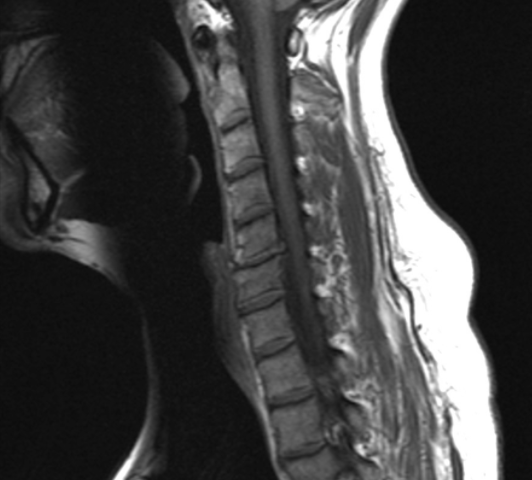

스마트폰를 손에서 놓지 않고, 하루종일 컴퓨터 모니터를 보며 생활하는 현대인들의 고질적인 질병 중 하나가 바로 목디스크입니다. 목디스크는 경추 추간판탈출증이라고도 부르는데, 경추는 7개의 등꼴뼈로 이루어진 척추의 맨 윗부분을 말하며 추간판은 디스크를 말합니다.

디스크는 우리 몸에서 목의 운동을 돕고, 목의 충격을 완화하여 척추뼈가 밀리거나 부딪히지 않도록 보호하는 쿠션과 같은 역할을 합니다.

하지만 나이가 들어가면서 목의 디스크 또한 노화되기 시작하고 핸드폰, 컴퓨터 모니터를 자주 사용함으로 인해 거북목, 일자목 등 체형의 변화가 오면서, 경추의 디스크가 후방으로 돌출되는 목디스크 질환이 생길 수 있습니다.